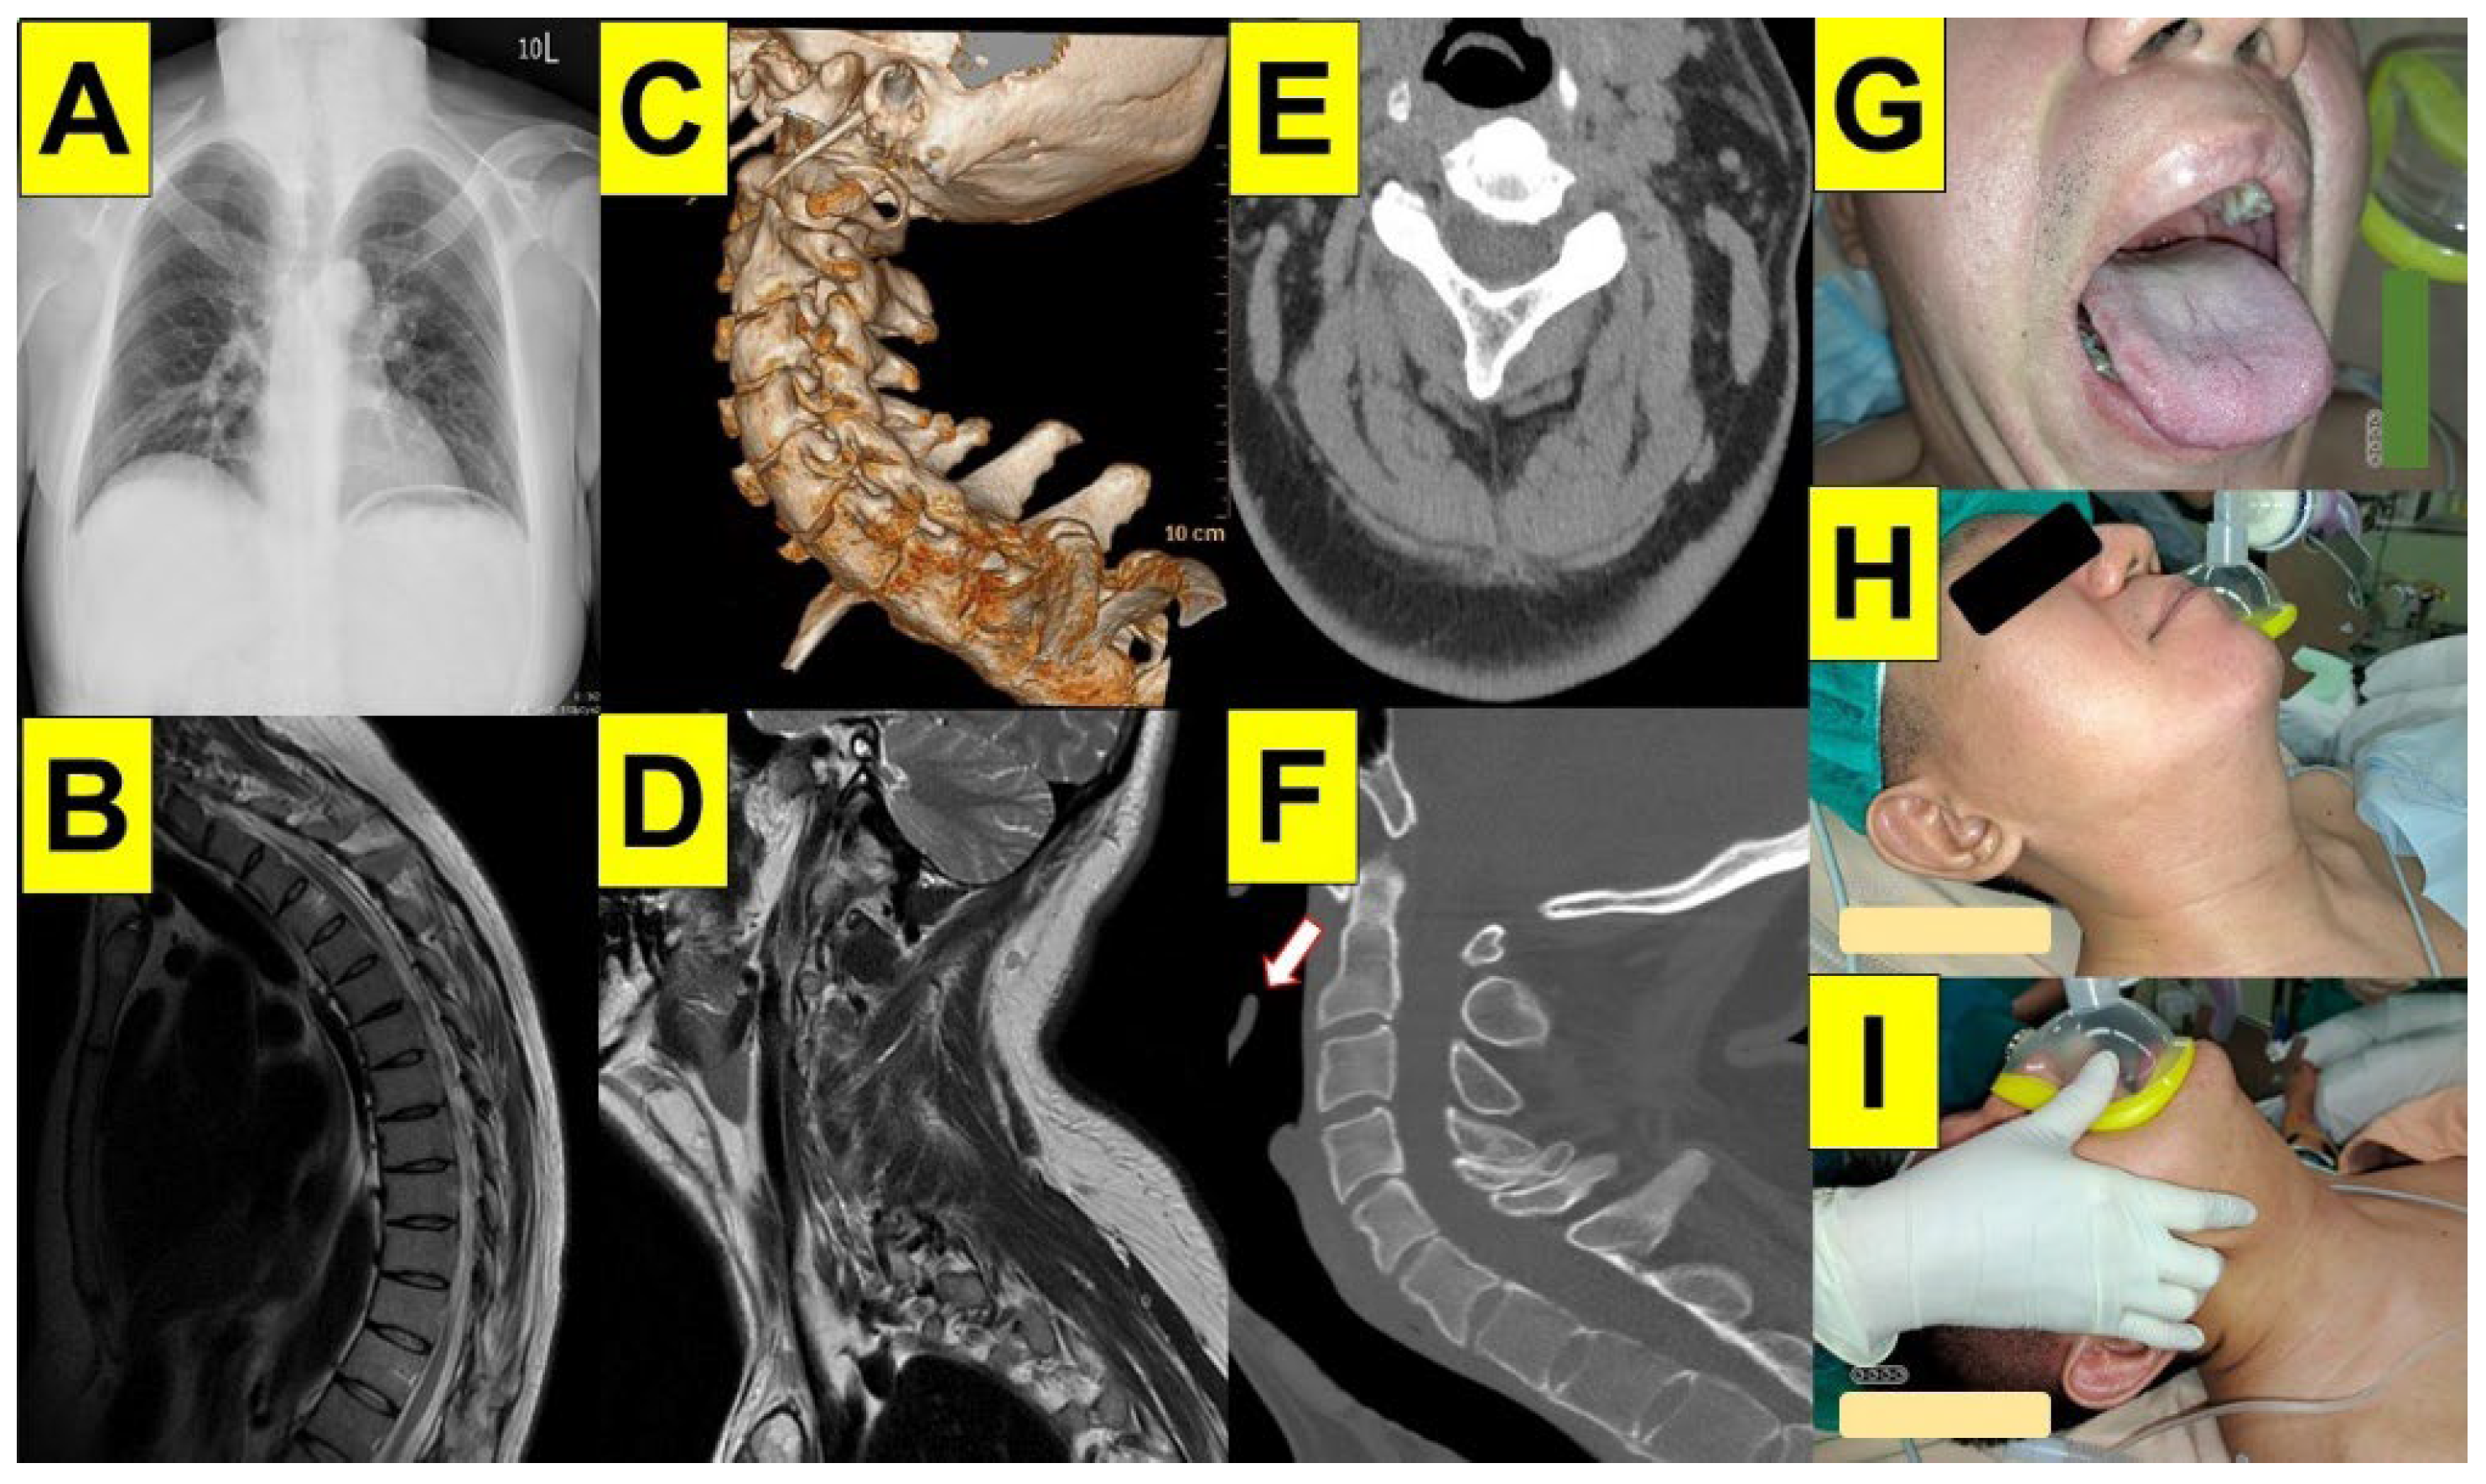

5.4. Ankylosing Spondylitis

5.5. Obesity